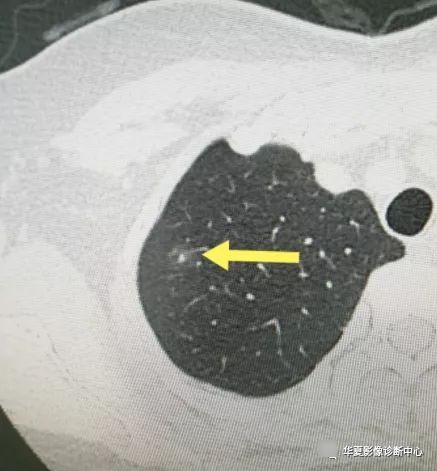

另外还有很多早期一些的磨玻璃结节的肿块,在工作中、生活中也会经常遇到。

肺磨玻璃密度结节处理办法因人而异,那么我们应该如果去正确的对待和治疗呢?

【 患者|从肺结节到肺癌,10个月影像记录,提醒我们正确对待肺结节处理】现在来看看Fleischner学会指南吧!

1、孤立的、直径小于5 mm的纯GGO不需要随诊。尤其是年老者,因为其在病理上代表AAH,少数为原位腺癌。扫描层厚必须为1 mm以确定其是否为真正的GGO。

2、孤立的、直径大于5 mm的纯GGO,3月后复查,以观察病变是否消失。如持续存在,则每年复查,至少持续3年。病理上为AAH、原位腺癌和一少部分微浸润腺癌。不建议使用抗生素。PET检查价值不大。CT引导穿刺不推荐,阳性率较低。如果病变增大或病变密度增高,可采取手术治疗,术式推荐胸腔镜楔形手术、肺段或亚段切除。